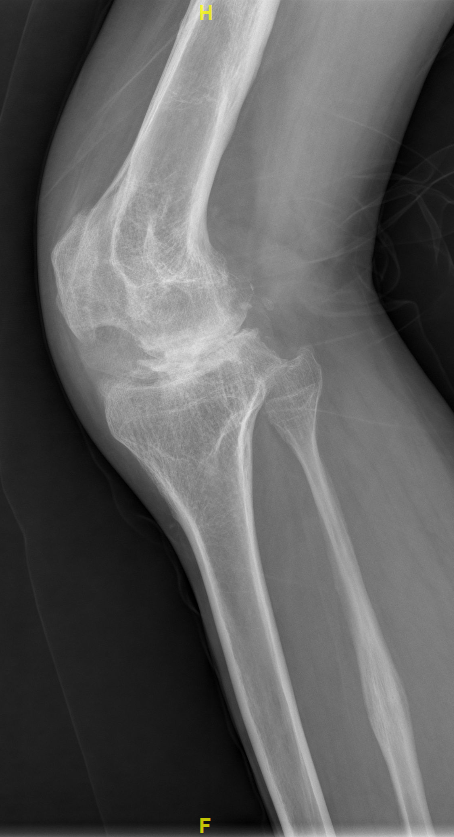

3、影像学检查

检查结果显示右下肢外翻畸形15度,股骨远端关节外畸形5度,髌股关节骨性融合,膝关节畸形发育。